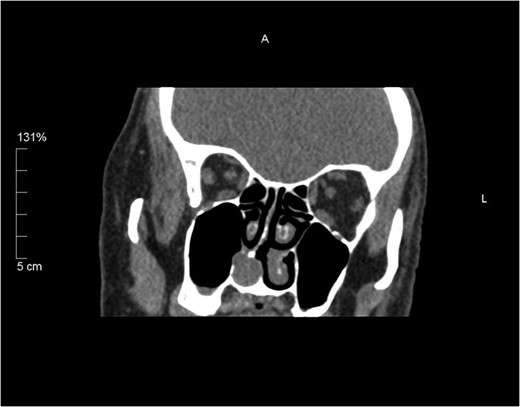

A 76-year-old male patient was referred to the ENT department with a history of right-sided nasal obstruction and rhinorrhoea. Clinical examination, revealed a polypoidal mass in the right inferior turbinate and deviation of nasal septum to the right. He had a past medical history of hypertension, angina and benign prostatic hypertrophy. A computed tomography (CT) scan of the paranasal sinuses confirmed the swelling of the right inferior turbinate, touching the nasal septum and floor, in addition to the septal deflection (Fig. 1). Clinically, a diagnosis of benign nasal tumour, most likely inverted papilloma, was made. As the lesion was not suspicious of a malignant pathology, a pre-operative magnetic resonance imaging (MRI) was not requested. The patient elected to have a wide local excision of the lesion. A septoplasty was carried out to allow access. Intra-operative findings confirmed a large polypoidal mass originating from the right inferior turbinate extending into the adjacent part of the lateral wall of the nose. It was felt that surgical excision with good margins of clearance was achievable; therefore, endoscopic medial maxillectomy including removal of inferior turbinate was performed. The patient recovered well from the procedure and was discharged the following day.

Coronal unenhanced CT sinus showing a 15 mm rounded soft tissue lesion arising from the right inferior turbinate thinning the medial wall of the right maxillary antrum and slightly bulging in to the sinus.